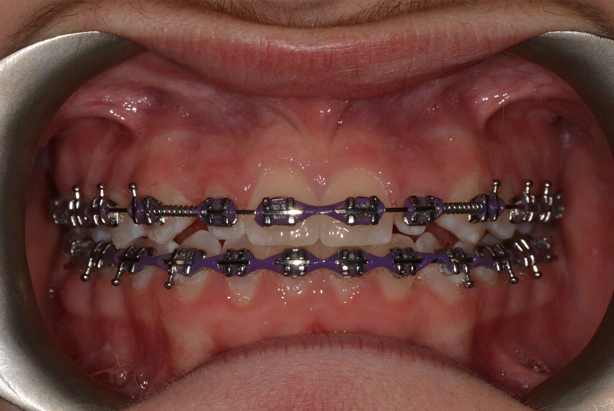

This patient was referred by a dentist who suspected the 23 would become impacted. After conducting a comprehensive orthodontic evaluation, it was decided that we would extract the 63 and make space for the tooth with the hope that it may erupt spontaneously.

After a period of time with clinical and radiographic monitoring, the patient was sent back to the dentist for a simple exposure and bonding.

This tooth has now come down significantly and we are now in the final stages of treatment.